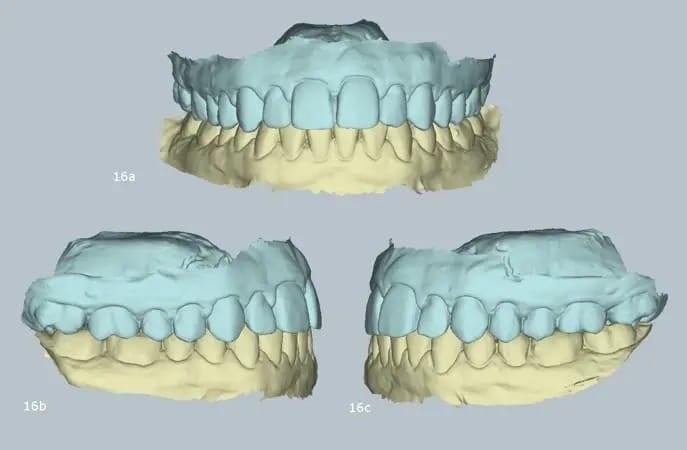

Более того, окончательная крепление виртуального артикулятора продемонстрировало точное соответствие между максимальной интеркуспацией пациента и истинной дугой смыкания. Такое выравнивание отражает достижение ортопедической стабильности — непременного условия для долгосрочного здоровья зубов, функционального прикуса и стабильности результатов лечения (фото 16).

Фото 16a–c: Крепление виртуального артикулятора с помощью MODJAW, демонстрирующее ортопедическую стабильность.